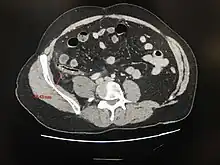

Appendicite aiguë perforée

Scanner abdominal : distension de l'appendice, infiltration de la graisse péri appendiculaire, pneumopéritoine localisé - l'IRM abdominale est également très fiable pour le diagnostic[56].